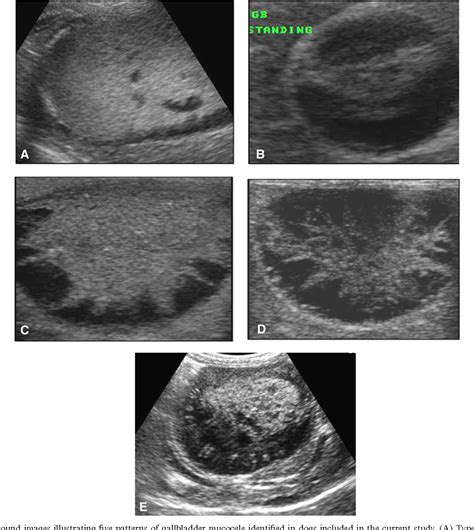

Ultrasound The initial imaging choice to detect gallstones, thickened gallbladder walls, and pericholecystic fluid.

• gallbladder rupture ultrasound